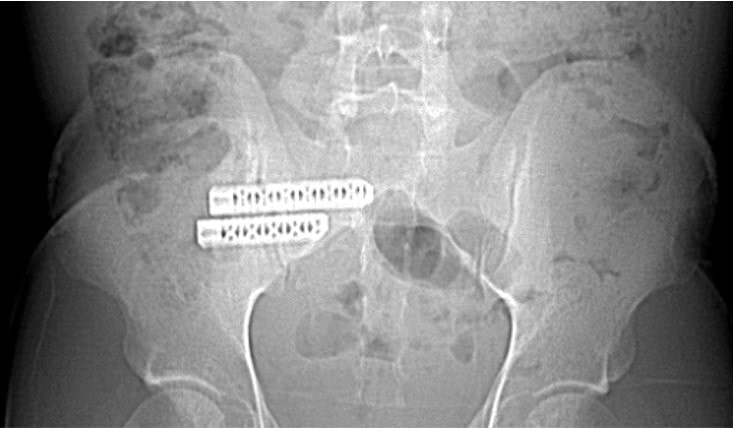

Orthobiologic injections could have been considered to help support the lax SI joint ligaments and restore stability. However, under the care of an orthopedic surgeon, the patient opted for an SI joint fusion instead.

The two large screws visible on the left pass through the SI joint into the sacrum. While this fusion stabilizes the joint, it also eliminates its natural movement. The SI joint is designed to absorb and distribute energy, and this functionality is lost after fusion. As a result, the energy that would typically dissipate through the SI joint is redirected elsewhere in the pelvic region.

When the patient resumed running just two months after the fusion surgery, the stress that the SI joint would typically absorb was instead redirected to the symphysis pubis. This excessive strain led to the rapid onset of severe osteitis pubis. Imaging studies (X-ray and CT scan) revealed significant damage: the normal space within the symphysis pubis, which houses the fibrous disc, had disappeared entirely, and the surrounding bone exhibited marked erosion.